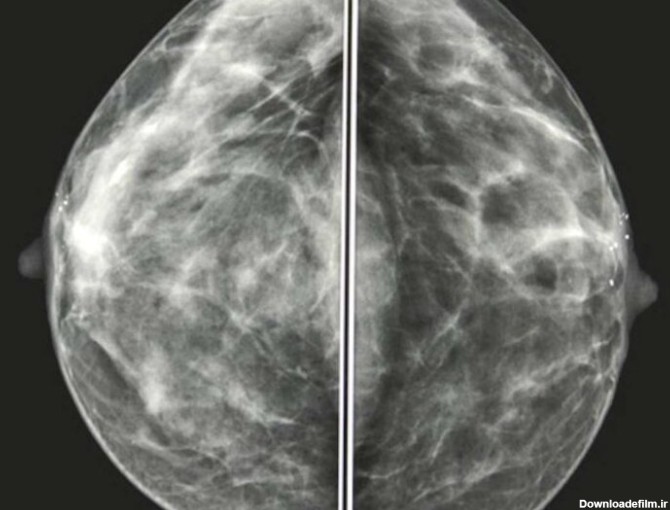

ماموگرافی، تصویربرادی از سینه و از مهمترین ارکان تشخیص سرطان سینه یا هر بیماری سینه است. این سرطان بین خانمها شایع است و باید مرتب سلامت سینه را چک کرد.

ماموگرافی توانایی پزشک را در تشخیص توده های کوچک افزایش می دهد. وقتی بیماری سرطان در مراحل اولیه باشد احتمال درمان کامل بیماری بسیار بالا است.. استفاده ازماموگرافی تشخیص رشد غیر طبیعی بافت درون مجاری شیری را امکان پذیر می سازد. این تومورهای سرطانی در صورتیکه در مراحل اولیه جراحی و خارج شوند آسیب چندانی برای فرد ایجاد نمیکنند. ماموگرافی تنها روش ثابت شده تشخی ... | انجام کلیه امور مربوط به سونوگرافی، رادیولوژی، ماموگرافی، پانورکس و سنجش تراکم استخوان به صورت دیجیتال واقع در غرب استان تهران (شهرک اکباتان)

ماموگرافی شکل و ظاهر سرطان سینه در ماموگرافی